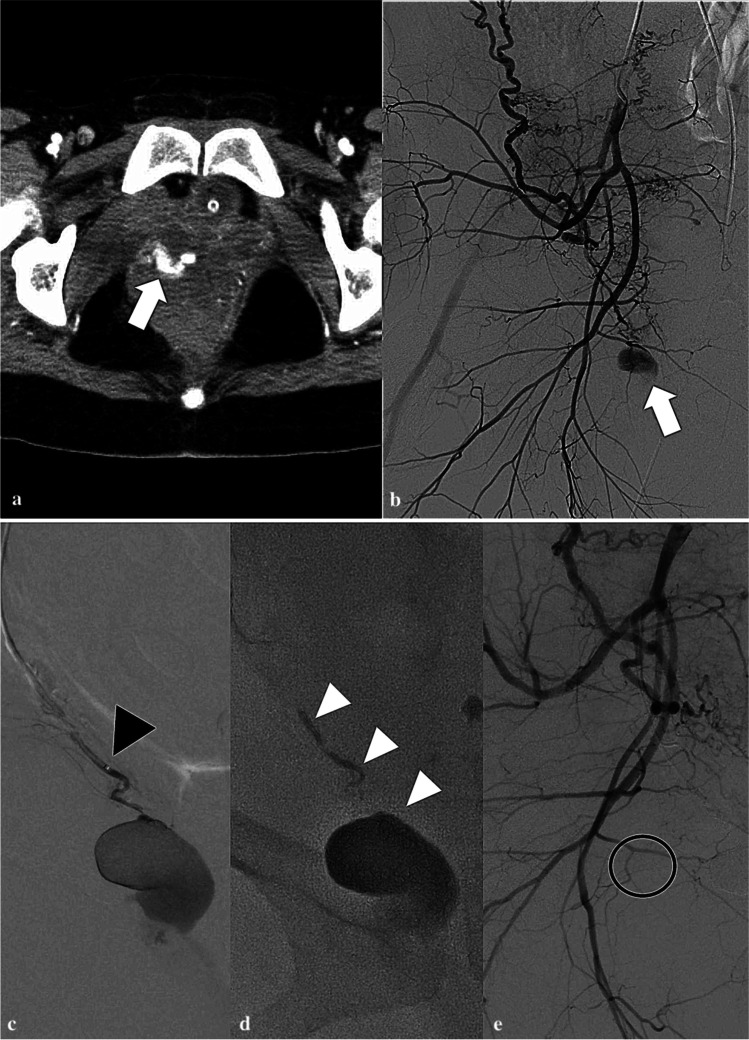

Fig. 1.

A typical case of superselective transcatheter arterial embolization. A 32-year-old woman with right vaginal hematoma presenting with postpartum hemorrhage after vaginal delivery. a Pre-procedural contrast-enhanced computed tomography shows extravasation of contrast medium in the right vaginal wall (white arrow). b Right internal iliac arteriography demonstrates a pseudoaneurysm from the right vaginal artery (white arrow). c Superselective angiography from the right vaginal artery; the black arrowhead points to the tip of the microcatheter. d The right vaginal artery was embolized with 33% NBCA-lipiodol mixture (white arrow heads). e The right internal iliac arteriography after embolization demonstrates disappearance of the pseudoaneurysm (black circle)